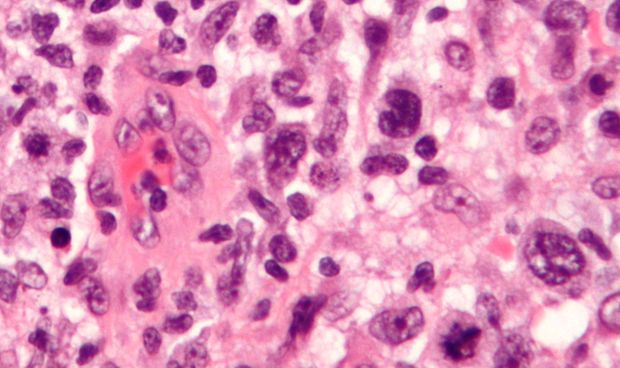

Según el coordinador de la guía, Miguel Ángel Canales, el objetivo es “proporcionar a los profesionales implicados en el cuidado de los pacientes con esta enfermedad una serie de recomendaciones sobre su manejo, principalmente desde el punto de vista terapéutico, ya que no existen evidencias sólidas para definir el tratamiento estándar de este tipo de procesos”. En ese sentido, los linfomas T “son un grupo muy heterogéneo de enfermedades que presentan una baja incidencia –representan el 10-15% de todos los linfomas- y que se caracterizan por su agresividad clínica”.